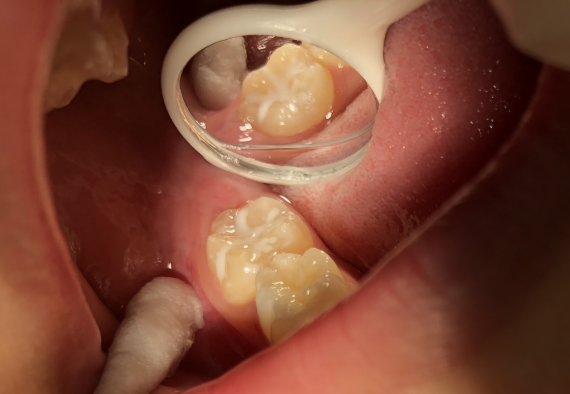

窝沟封闭的效果:

阻止细菌在窝沟内积存

阻断窝沟内细菌的营养来源

消除了窝沟发育缺陷

封闭牙齿釉质表面多孔结构

但是,窝沟封闭并不是一劳永逸的!

窝沟封闭有一定的脱落率!

窝沟封闭后需要定期复查!

如果封闭剂出现磨耗或脱落,

仍有可能出现窝沟龋。

因此,定期复查非常重要!

医生建议,封闭后的 3 个月、半年、

一年以及之后每一年都应当定期复查